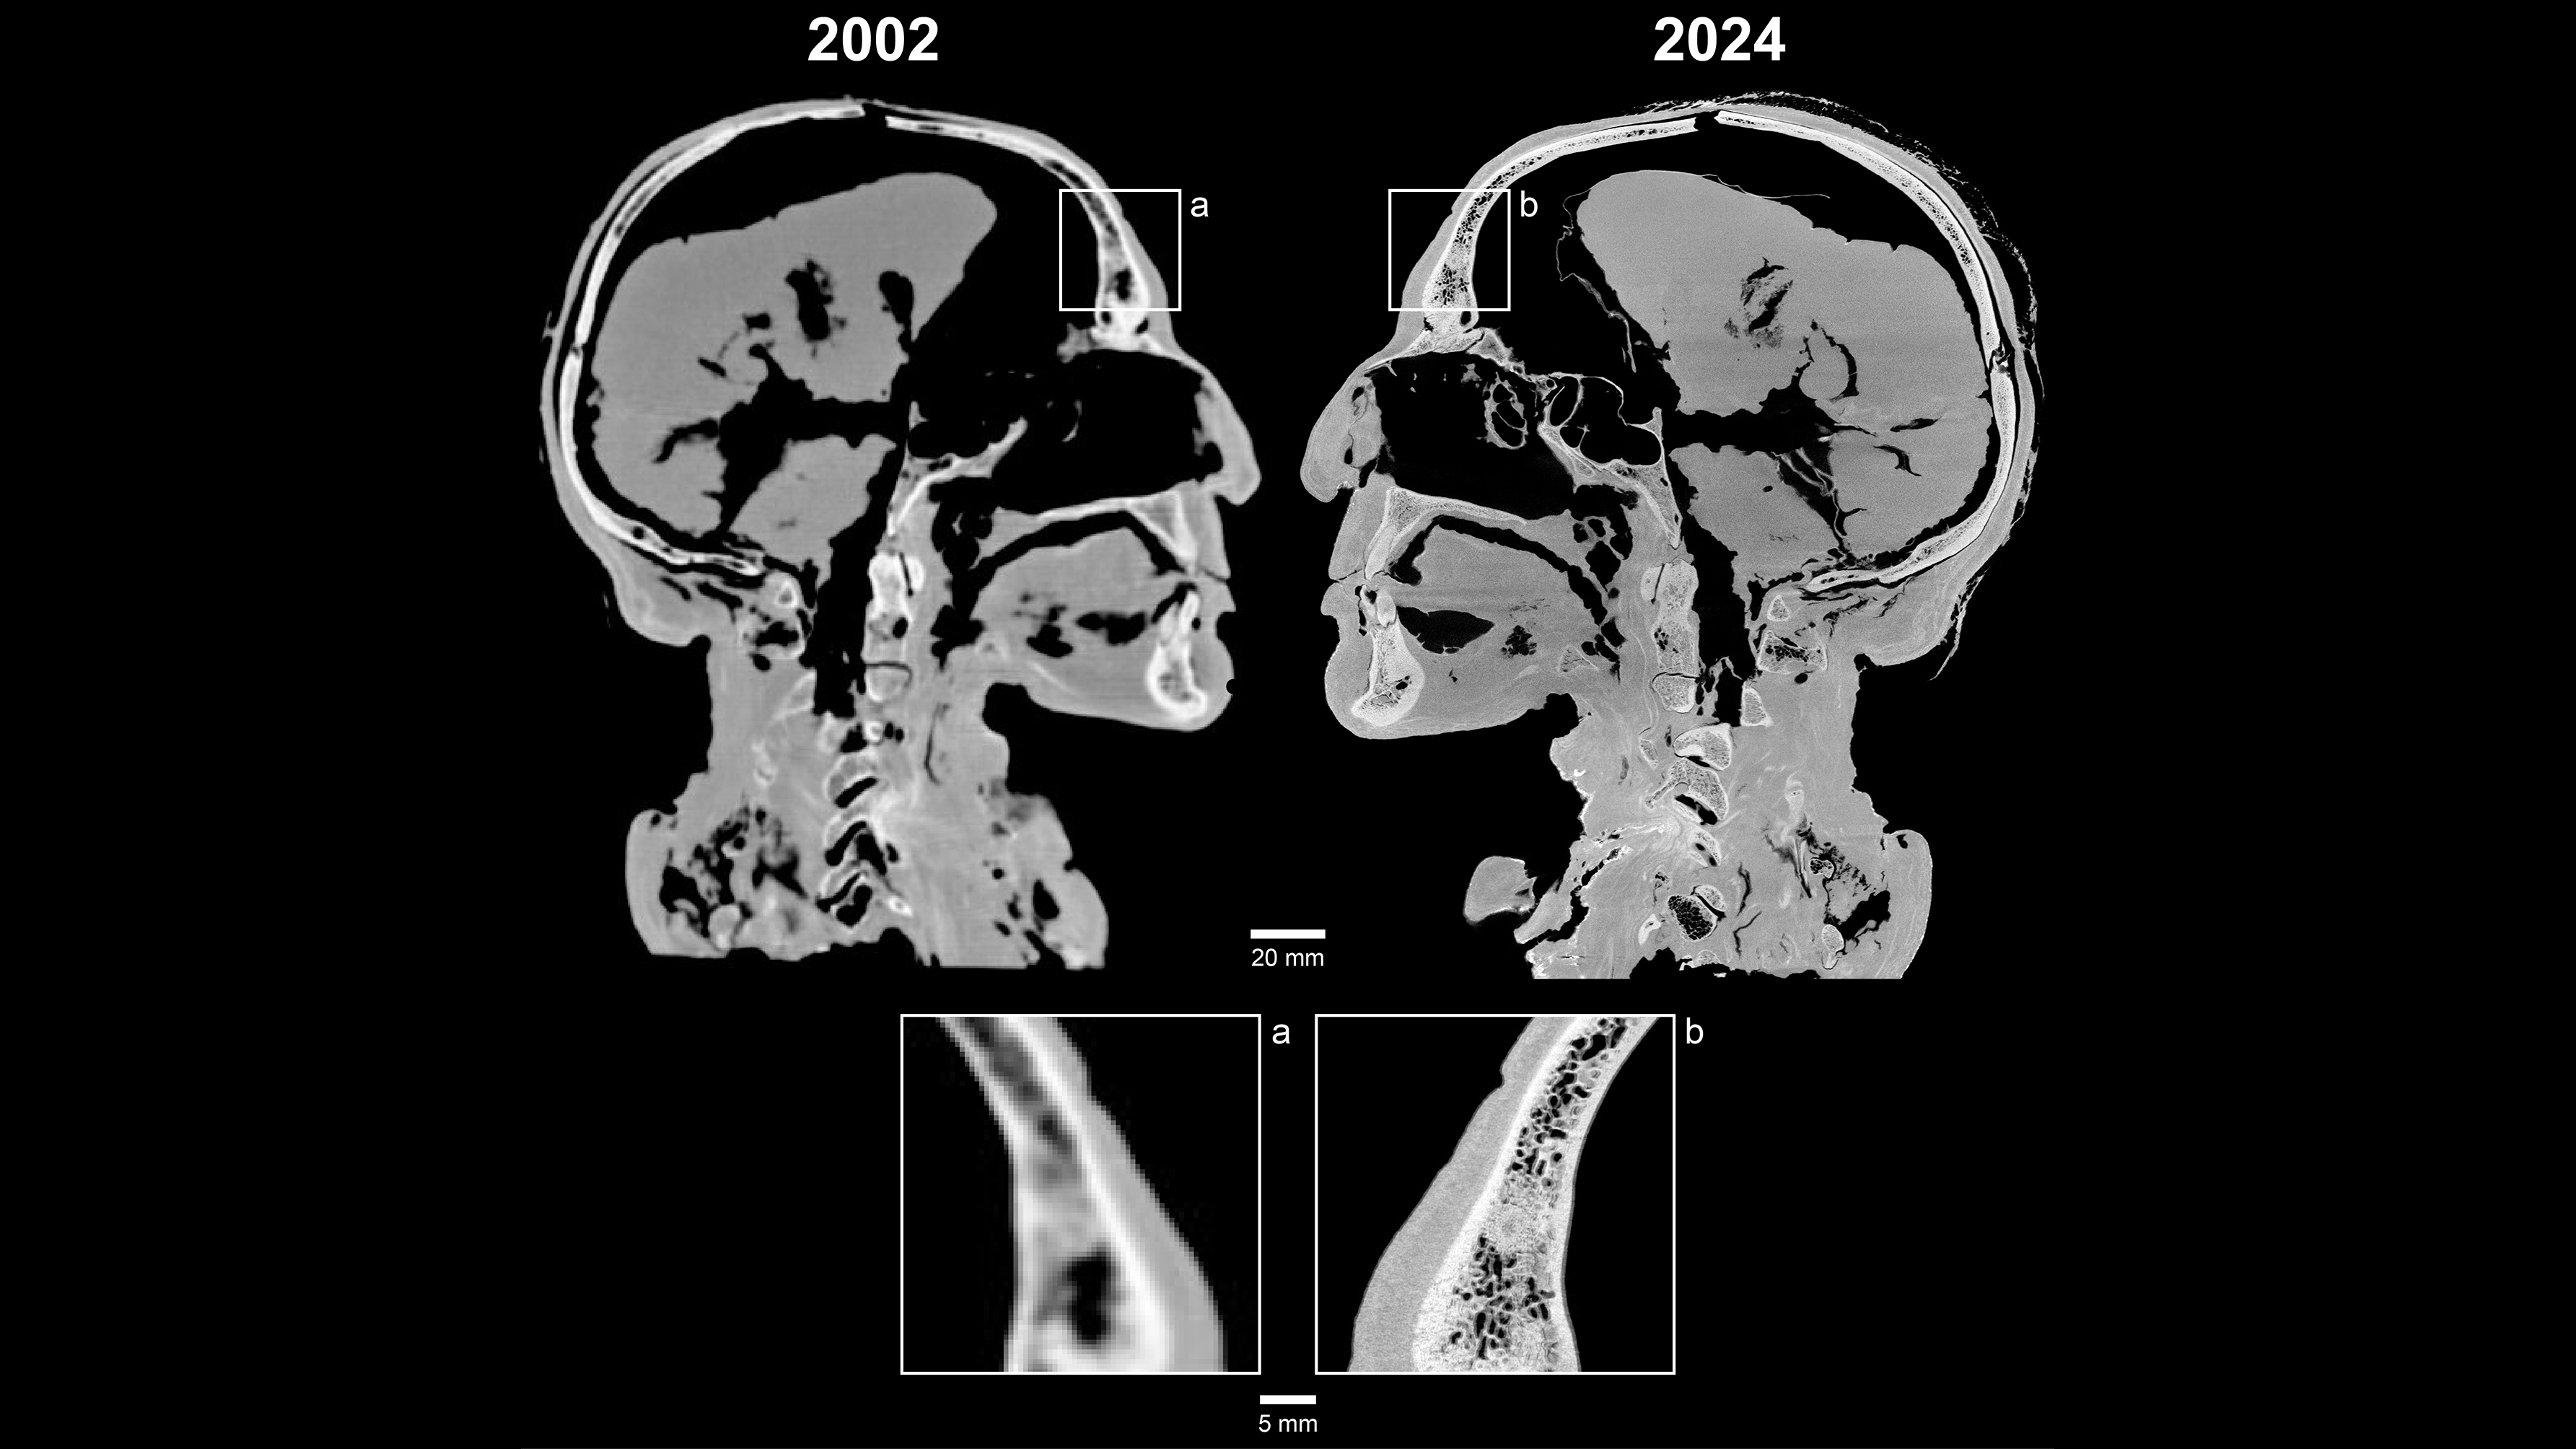

Hovedet har været scannet én gang før – i 2002. På de gamle scanninger kunne man kun se tænderne som utydelige pløkker. Sammenligner man de nye scanninger med de gamle, er det fuldstændig som at have fået nye briller, siger Ole Nielsen. Opløsningen i de nye billeder er 422 gange bedre end i de gamle. Det gør en forskel.

”De nye scanningsbilleder er så flotte på grund af den gode kontrast, som gør det nemt at se forskel på forskelligt væv,” forklarer Kasper Hansen.

”Fordi Tollundmanden har ligget i en syrlig mose i over 2000 år, er meget af hans knoglemineral udvasket. Derfor er kontrasten mellem knogler og det bløde væv mindre end normalt. Men på en mikro-CT-scanner kan vi opnå bedre kontrast på de forskellige væv og se mange flere detaljer,” forklarer forskeren:

”Forskellen på en almindelig CT-scanner og en mikro-CT-scanner er som at gå fra et gammelt digitalkamera til et splinternyt.”